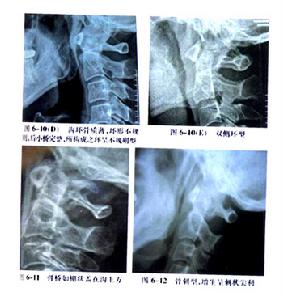

8.頸椎X 線平片 正側片、左右斜位及張口位片示,頸椎生理曲線變直、反張、成角或中斷。骨質增生。環椎後結節上翹,齒狀突距兩側塊距離不等寬。

1.X 線頸椎可見頸椎椎體、間盤、鉤突關節退變和項韌帶鈣化,頸椎生理曲度變直等改變。